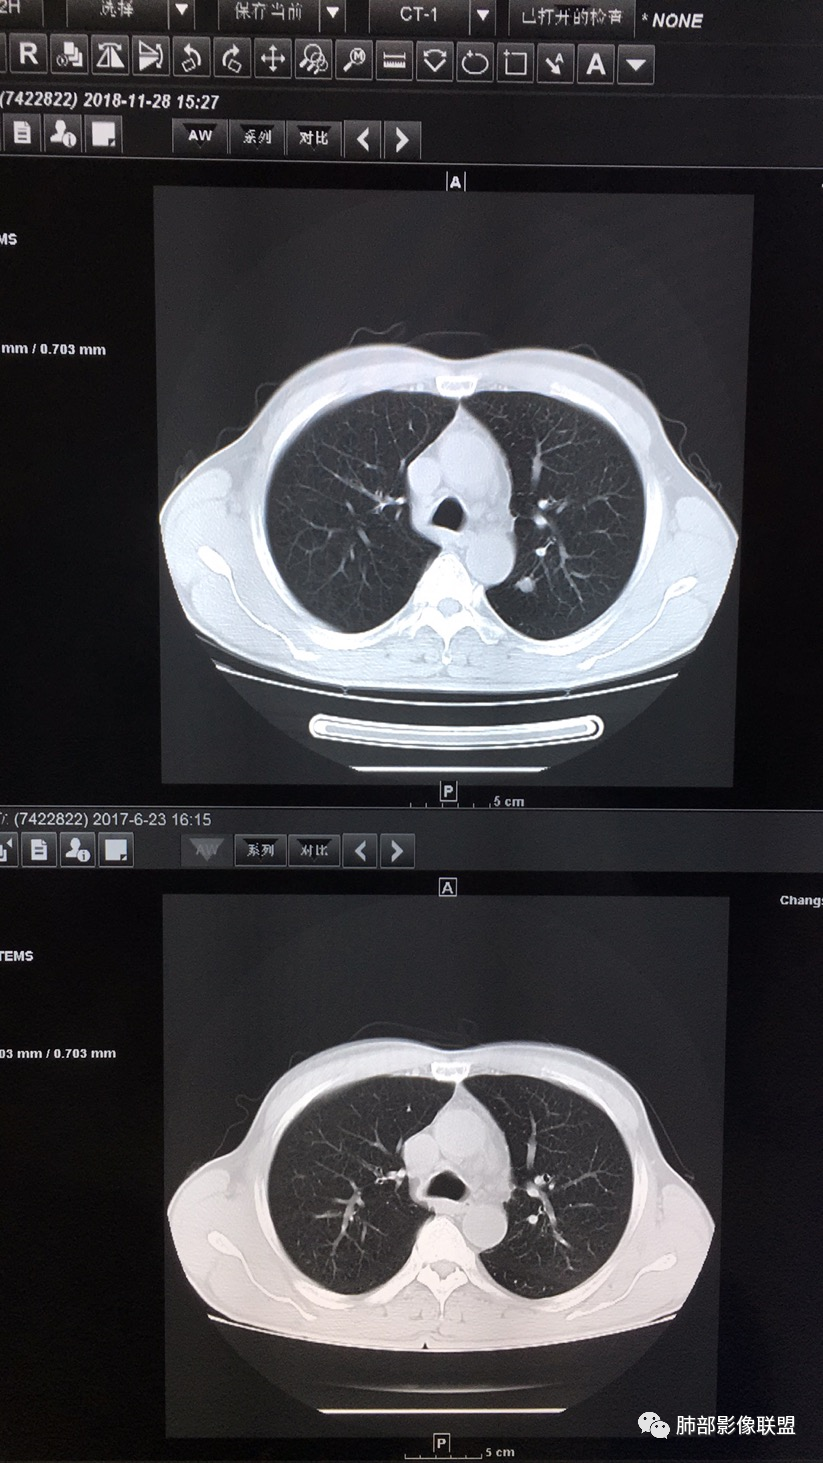

57岁男性,长期吸烟史,有血吸虫病史,有粉尘接触史。发现纵隔淋巴结肿大2年,声嘶伴咳嗽咳痰半月。两年前胸部CT见左上肺尖后段结节并肺门淋巴结肿大,治疗后左上肺结节消失。目前胸部CT:肺气肿,左上肺尖后段见条索影(原来结节治疗后的改变?),肺门、纵隔淋巴结肿大并融合,似见薄壁包膜样强化。考虑淋巴结结核可能性大,注意鉴别淋巴瘤、转移、结节病等。

南边:纵隔淋巴结肿大病史2年,右上肺结节消失,这个病史值得玩味淋巴结肿大,中纵隔

左肺门,后纵隔

肺内好像就是慢阻肺痰栓

淋巴结有融合

这次的症状与气管受压有关,不一定可靠

病史,吸烟老年男性,这是个不好的病史问题来了,原来有左上肺结节并淋巴结肿大,治疗后好了,现在又有淋巴结肿大

这是17年和18年在我院做的CT平扫